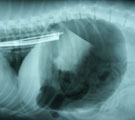

胃内視鏡でスポンジ確認 レントゲンにて内視鏡での摘出困難と判断

経過:一般状態良好。24時間絶食後、全身麻酔下にて内視鏡検査を行った。ただちに胃内にスポンジを確認したが、把持鉗子でつかんでも噴門(胃の入り口)を通過できなかった。処置中、レントゲンで異物があまりにも大きく内視鏡では摘出困難と判断した。止む無く、胃切開術に移行し、異物を摘出した。スポンジは水分を含んで元の大きさの約1.5倍に膨らんでいた。